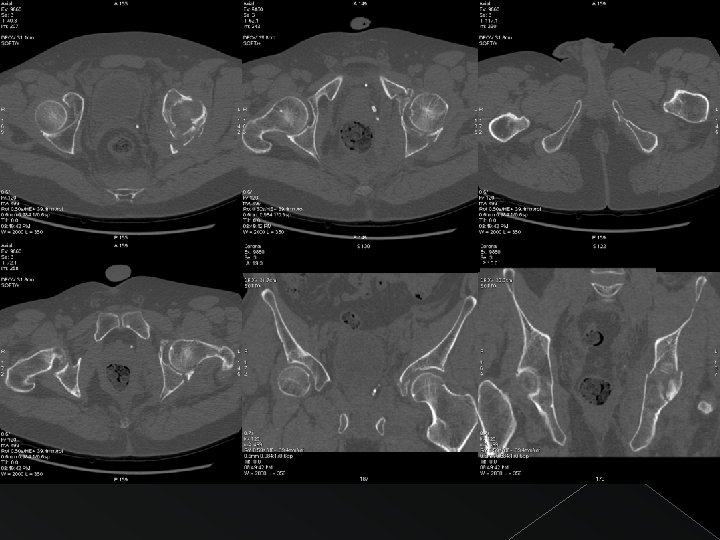

Caso 1

Disrupción del anillo obturador + extensión a pala iliaca FRACTURA BICOLUMNARIA